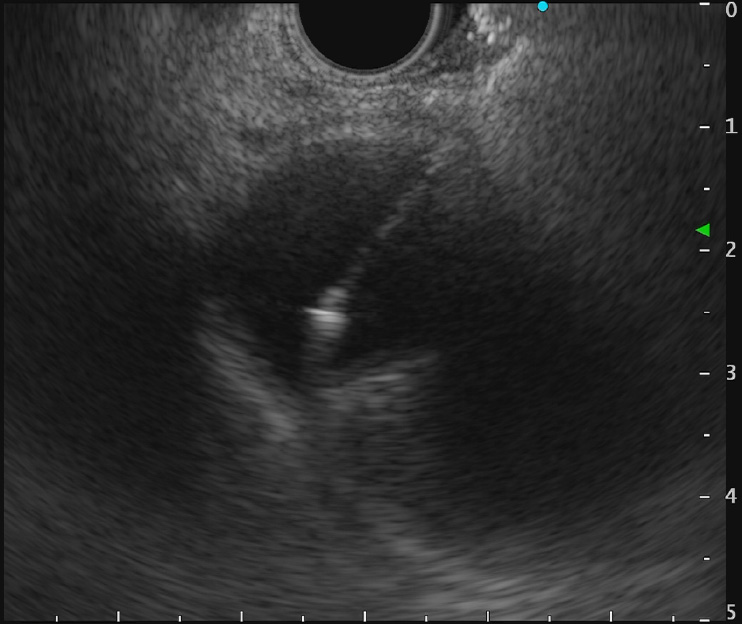

重症急性膵炎後のWONに対するEUS下膿瘍ドレナージ